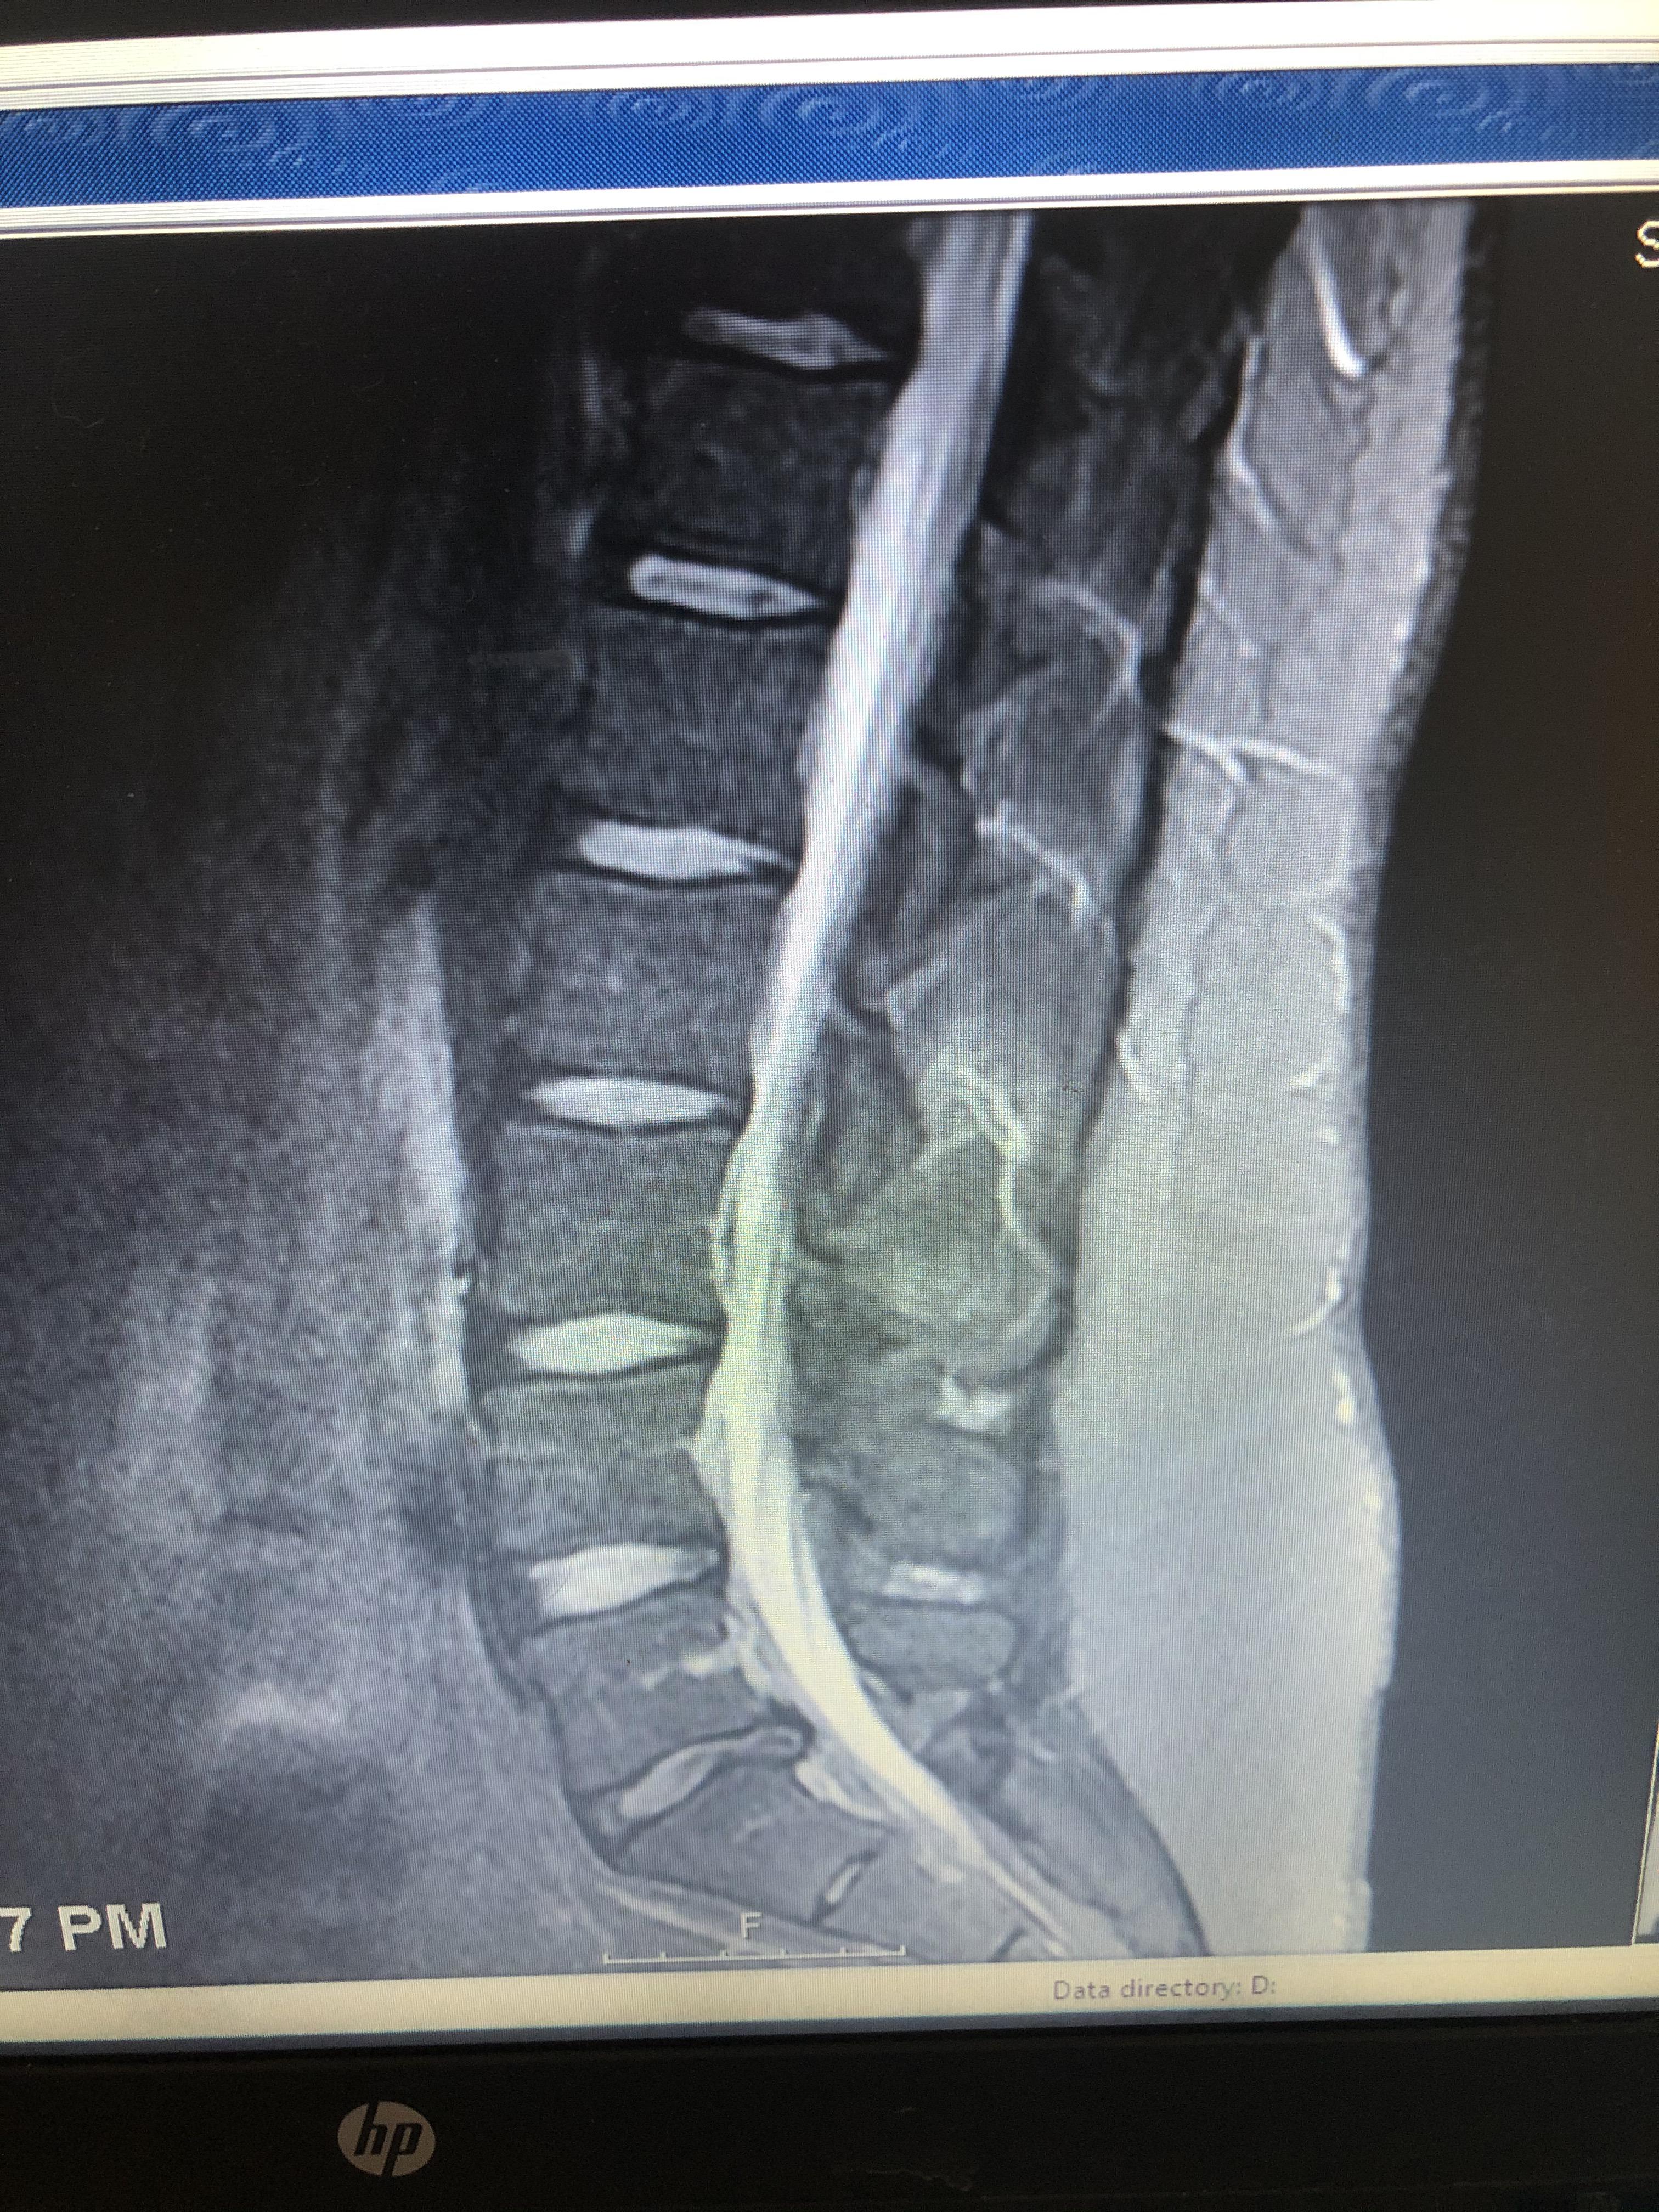

Large L5 S1 Disc Herniation MRI Stock Image C043/0183 Science Herniated Disc Hip Pain L5-S1 Treatment options range from conservative interventions to surgical. A herniated disk occurs when some of the softer material inside the disk pushes out through a crack in the tougher outside of the disk. Typically, a dull ache or. Pain in the lower back, buttocks, outer sides of the thigh and calf, top of the foot, and the big toe. Discs. Herniated Disc Hip Pain L5-S1.

Spinal Cord Injury L5S1 Disc Herniation with Compression of Cauda Herniated Disc Hip Pain L5-S1 This is because the nerve. Weakness in the hip and knee muscles causing difficulty with lifting the leg, crossing the legs, or straightening the leg. Pain in the lower back, buttocks, outer sides of the thigh and calf, top of the foot, and the big toe. Typically, a dull ache or. A herniated disk occurs when some of the softer. Herniated Disc Hip Pain L5-S1.

Lumbar Disc Herniation at L5 S1 with Film Print Stock Photo Alamy Herniated Disc Hip Pain L5-S1 Discs separate the vertebrae (spinal bones), cushioning the spinal column and allowing for movement between vertebrae. Treatment options range from conservative interventions to surgical. Weakness in the hip and knee muscles causing difficulty with lifting the leg, crossing the legs, or straightening the leg. Typically, a dull ache or. This is because the nerve. A herniated disk occurs when some. Herniated Disc Hip Pain L5-S1.